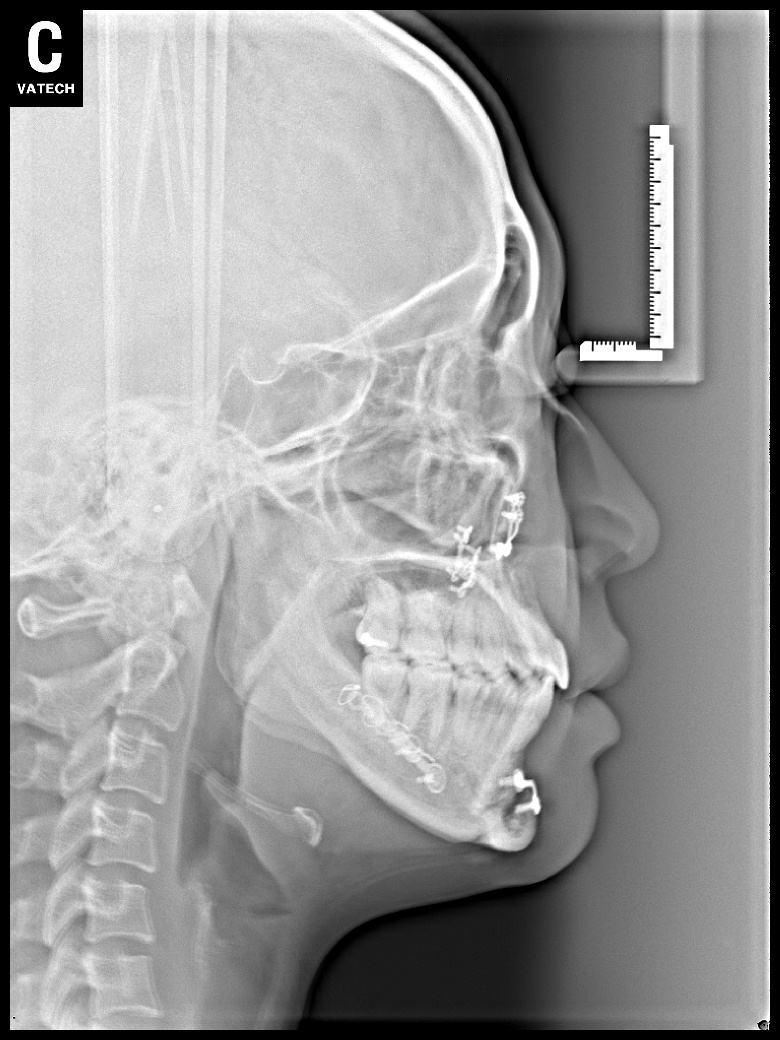

치료 후 사진입니다.